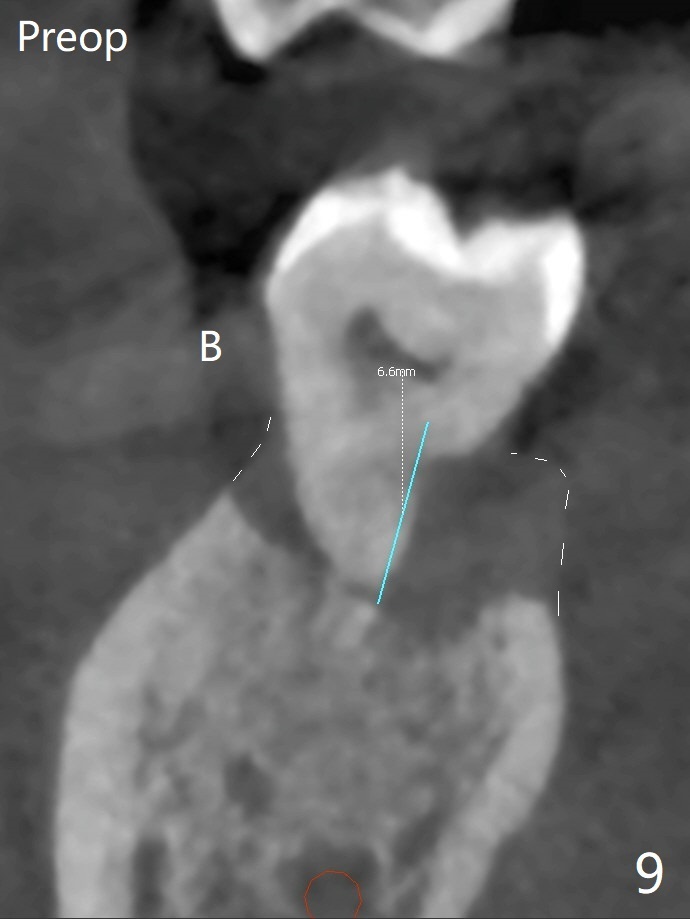

After removing the fractured apices of the tooth #31 (Fig.1,2), it is extremely difficult to start osteotomy with 7.3 mm stopper free hand. Since sticky bone (Fig.3,4) and PRF membrane are available, socket preservation is performed with bone condenser and PGA (Fig.5). If a surgical guide were fabricated, immediate implant would finish quicker. The socket opening is almost closed without pain or swelling 8 days postop (Fig.6). Clinically, the ridge is apparently wide with enough keratinized gingiva 4.5 months postop. The original ridge height seems to restore as the sticky bone undergoes condensation vertically (Fig.7, as compared to Fig.5). With bone graft, a 1.5 mm longer implant could be placed (Fig.8). The gingival pocket (Fig.9 white dashed line) seems to be an excellent cultivation bed for bone graft, although the latter also undergoes buccolingual shrinkage coronally (Fig.10).